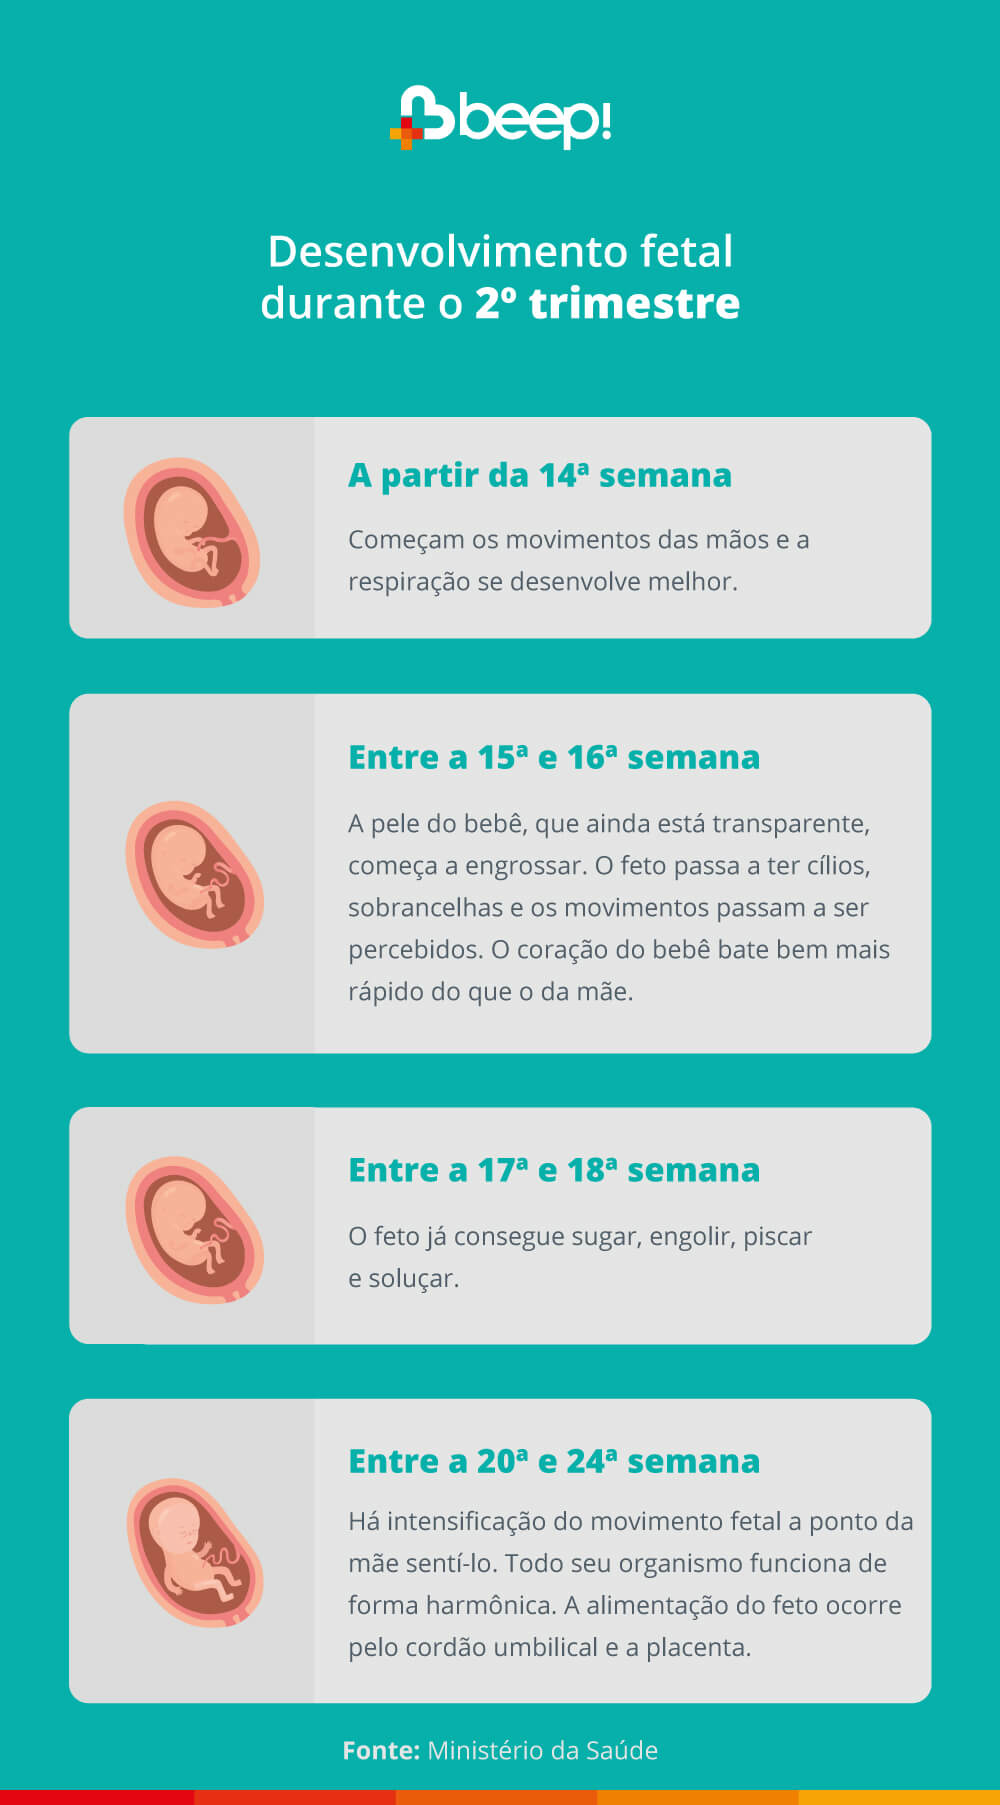

2º trimestre de desenvolvimento do feto

Durante o 2º trimestre, o feto começa a ficar mais desenvolvido. Abaixo, trazemos todas as mudanças do feto semana a semana: